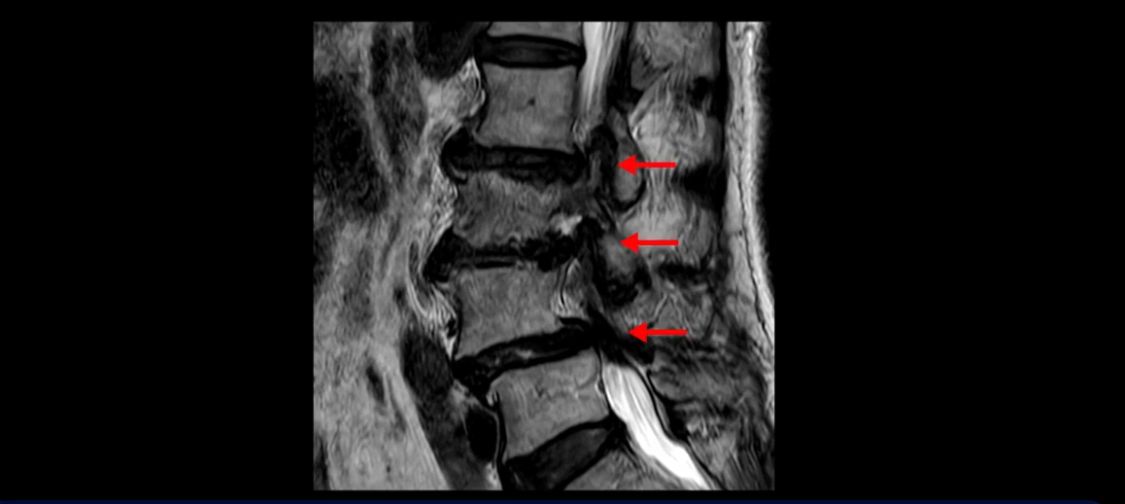

이분 MRI 보시면 허리 3마디의 퇴행이 매우 심합니다.

4번 5번에는 뼈가 밀려 나간 전방전위증도 있고,

또 척추관협착도 매우 심합니다.

척추관이 심하게 좁아져 있습니다.

이렇게 여러 마디가 안 좋고 뼈도 밀려 나가 있으니까 나사박는 수술해야 하는데, 대학병원에서도 수술을 한 번에 못 하고 두 번에 나눠서 해야 한다고 들으셨습니다. 왼쪽으로 신경가지가 빠져나가는 추간공도 많이 좁아져 있습니다.